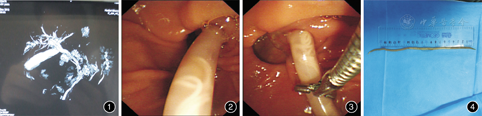

患者女,53岁。因"发作性上腹痛伴发热2 d"入院。患者平素喜好生冷蔬菜、瓜果等饮食,2个月前自诉有大便排出蛔虫史。入院后患者上腹痛基本缓解,仅感上腹不适。腹部B超提示:左肝管、肝总管及胆总管上段腔内扭曲的条索状偏高回声,考虑胆道蛔虫;磁共振胆管造影诊断:胆总管、肝总管及左肝管内异常信号,考虑蛔虫可能,肝左内叶及右叶异常信号,考虑感染,肝内胆管扩张(图1)。经讨论诊断"胆道蛔虫症"明确,有ERCP治疗适应证,于当日下午行急诊ERCP。ERCP诊治过程:十二指肠降部找见主乳头,主乳头位于憩室内,开口绒毛状,乳头开口红肿,切开刀+导丝胆管插管顺利。胆管造影显示:胆总管显影清晰,肝总管及胆总管内见一长条状透亮影,胆总管直径1.0 cm,肝内胆管扩张。行EST小切开(切开直径0.6 cm),循导丝用取石球囊于肝总管上端向下拖拉,拉至胆总管下端时见蛔虫体露出主乳头外,用鼠齿钳轻轻夹住露出乳头外的蛔虫,缓缓将整个蛔虫拖出胆总管至十二指肠腔,用鼠齿钳于肠腔内将蛔虫夹住,随镜一起退出,取出的蛔虫为活体蛔虫,测量长径为22 cm(图2,图3,图4)。取出蛔虫后置入鼻胆管引流,胆汁引流通畅。术后加强抗感染治疗,并给予驱蛔虫治疗,留置鼻胆管引流5 d,患者住院1周痊愈出院。术后1个月随访未见异常。